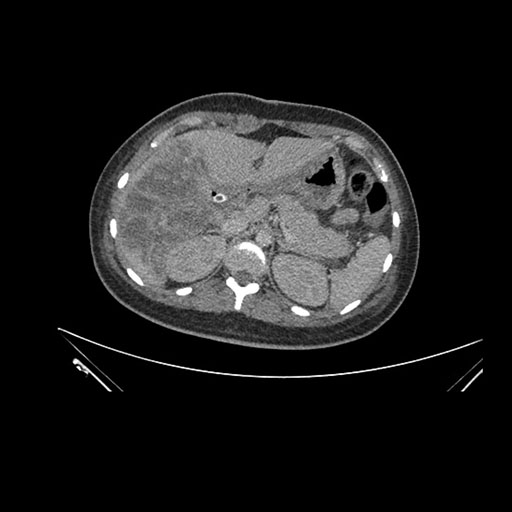

Axial Arterial

Imaging analysis

Based on initial findings, which issue(s) would you be most concerned about?